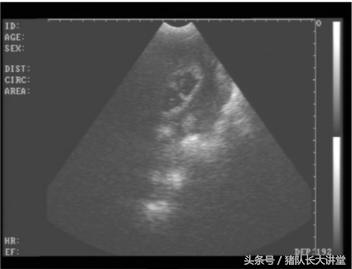

23天的B超图

2、这里只说下B超因为本人用的也比较多;

A、可以较为准确的测出是不是有小猪,具体使用办法,根据说明使用,大家也可以提出问题;注意,一般你检测有的就是有了,单是检测没有的时候应该多观察;